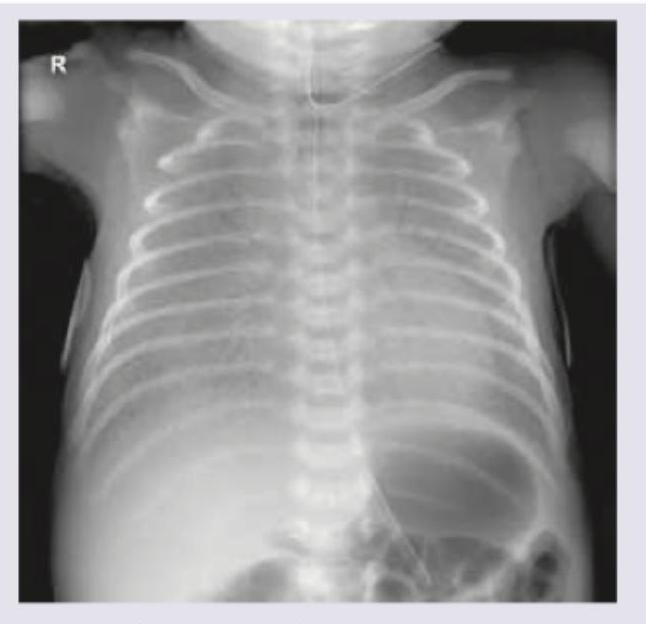

Question 8: Neonate born at 34 weeks with premature rupture of membranes develops respiratory distress. CXR was performed. All are considered in differential diagnosis except:

- D. Tetralogy of Fallot (Correct Answer)

Explanation: ***Tetralogy of Fallot*** - **Tetralogy of Fallot** is a **cyanotic congenital heart defect** characterized by VSD, pulmonary stenosis, right ventricular hypertrophy, and overriding aorta. - It presents primarily with **cyanosis** (not respiratory distress) and would show **normal or oligemic lung fields** on CXR, not the diffuse parenchymal lung disease patterns seen in RDS, pneumonia, or alveolar proteinosis. - **Not part of the differential diagnosis** for a preterm neonate with PROM presenting with respiratory distress and lung infiltrates on imaging. *Congenital pneumonia* - This is a significant concern in a neonate born prematurely with **premature rupture of membranes (PROM)**, as ascending infection is a known risk factor. - Chest X-ray findings can include **diffuse hazy infiltrates** or **patchy consolidation**, consistent with infections. - Would be considered in the differential diagnosis. *Hyaline membrane disease* - Also known as **respiratory distress syndrome (RDS)**, this is common in **premature infants at 34 weeks** due to **surfactant deficiency**. - The chest X-ray typically shows **diffuse reticulogranular ground-glass opacities** and **air bronchograms**. - Most common cause of respiratory distress in preterm neonates and a key differential. *Congenital alveolar proteinosis* - This is a rare genetic disorder where **surfactant proteins accumulate in the alveoli**, leading to impaired gas exchange and respiratory distress. - Chest X-ray findings often include **diffuse alveolar infiltrates** or consolidation, which can resemble other neonatal lung diseases. - Though rare, must be considered in the differential for neonatal respiratory distress.